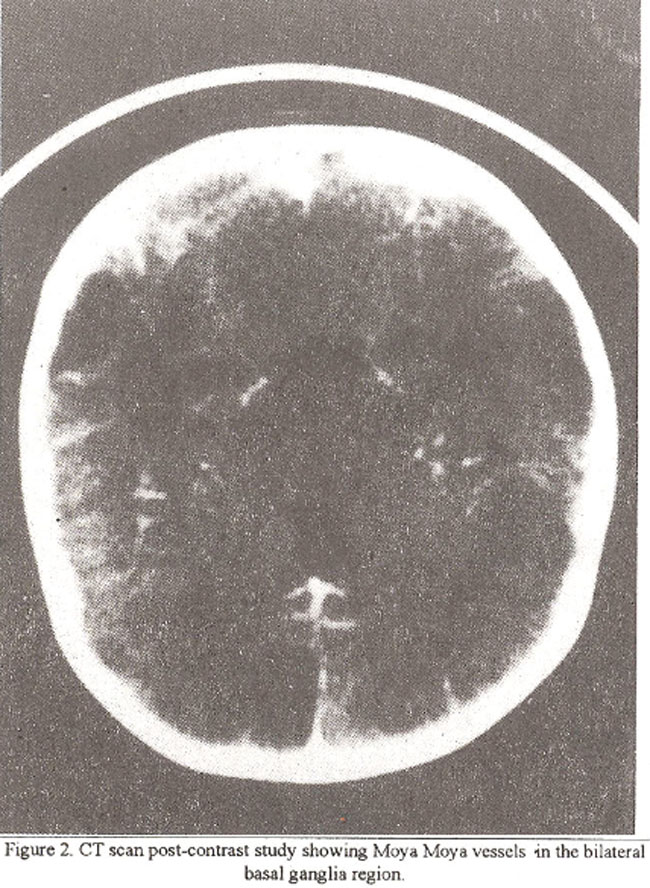

Circle of Willis was not visualized in all three patients who had CT scan. MRJ was able to detect small dilated tortuous signal void areas in the basal ganglia region in three patients (Figure 3).